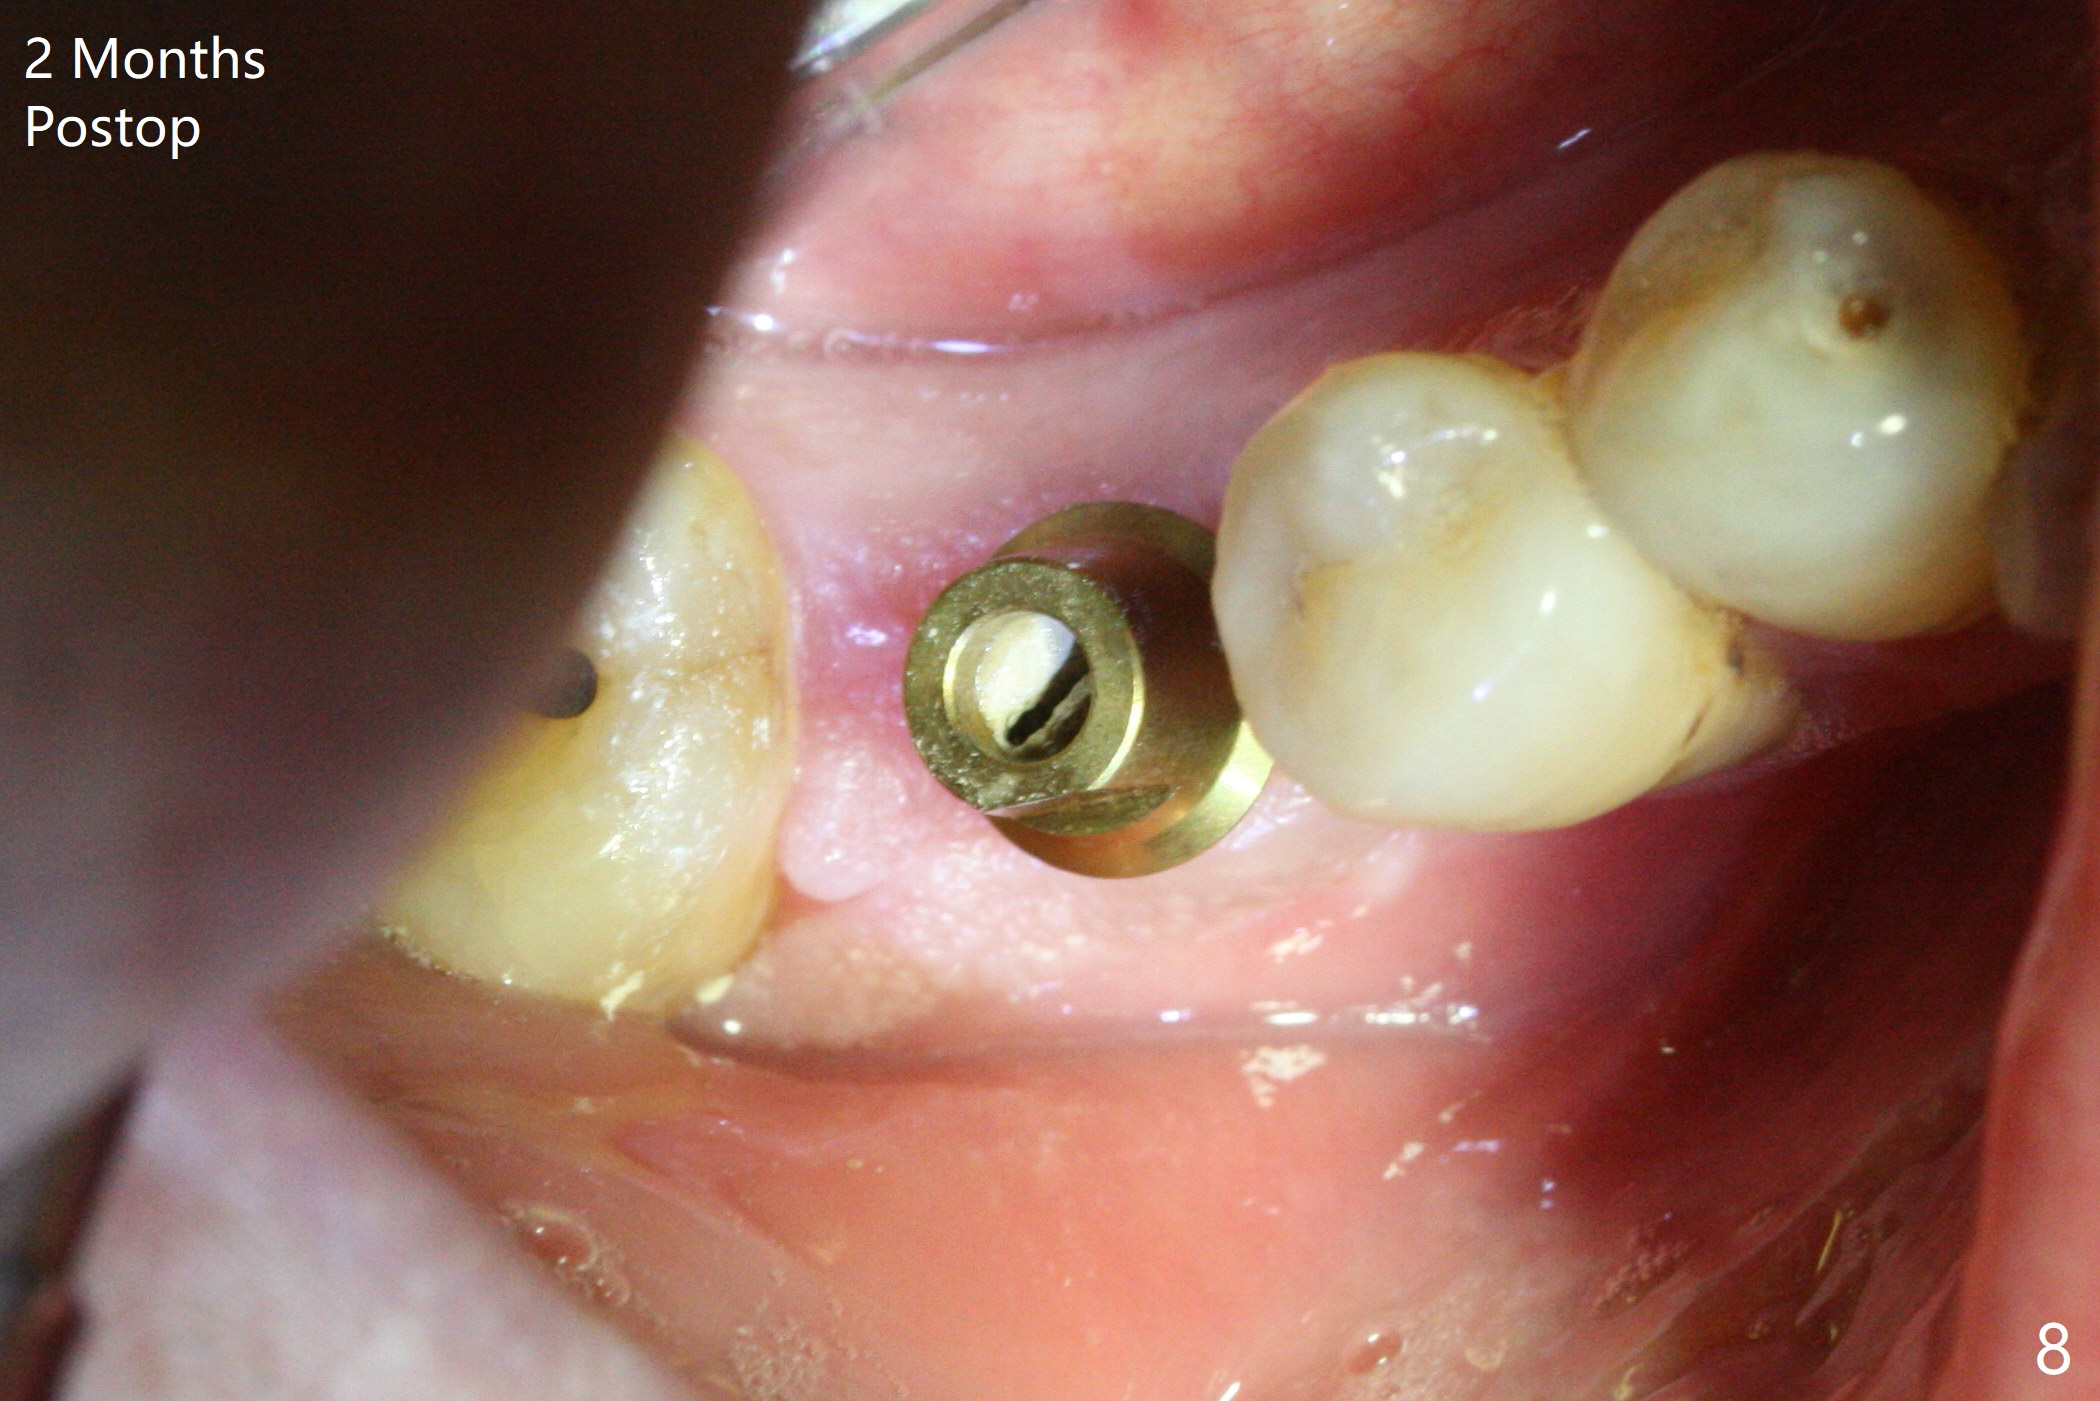

After extraction of the tooth #30, the mesiobuccal plate is found to be lost, corresponding to the fistula (Fig.1 <). Osteotomy is initiated in the flattened septum (lingual) for 13 mm (Fig.2). The patient feels pain when larger drills are being used. Marcaine has to be injected in an infiltration manner for pain control. When a 4.5x10 mm dummy implant is inserted with 55 Ncm, the end of the osteotomy (Fig.3 white line) is close to the Inferior Alveolar Canal (red dashed line). When a definitive implant (Fig.4: 4.5x11.5 mm) is placed with primary stability, there is an apical space (Fig.5 white double arrows). There is moderate postop pain. A shorter implant (10 mm) should be tried when the bone is dense. It will be associated with less pain. The fistula disappears 7 days postop (Fig.6). Although the patient appreciates that the pain is gone, there is atrophy mesiobuccally 2 months postop (Fig.7 *). The implant seems to be have been placed too buccally (Fig.8). With loss of the buccal plate, the implant should be placed away from it to prevent periimplantitis. The abutment is changed from 6.5x4(4) to 6.5x5.5 (3) mm with fabrication of a new provisional. The buccal margin is still supragingival 6 months postop and prep lower before impression. The mesial and distal sockets appear to have healed (Fig.9). When the crown is cemented, the mesiobuccal papilla is present (Fig.10 *), while the mesiolingual one is apparently absent (Fig.11 *). Using a temporary abutment and relining the provisional multiple times would increase the chance of rebuilding the missing papilla. The bone density around the implant increases 11 months post cementation (Fig.12). The dense (apparently cortical) bone seem to grow over the implant plateau 11 months post cementation (Fig.13 <).